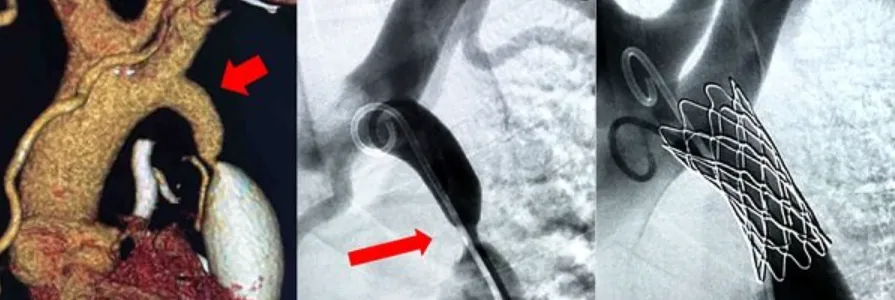

Các phương pháp điều trị hẹp eo động mạch chủ hiện nay bao gồm nong mạch bằng bóng kết hợp hoặc không kết hợp với đặt stent, và phẫu thuật. Trong đó, phương pháp can thiệp nong hẹp bằng bóng thường được ưu tiên sử dụng vì tính ít xâm lấn, hiệu quả cao, thời gian phục hồi nhanh và thời gian nằm viện ngắn [Nguồn: Vnah.org.vn, Timmachhoc.com]. Với phương pháp này, bác sĩ sẽ đưa một bóng nong vào từ động mạch đùi tới vị trí hẹp eo động mạch chủ. Bóng được bơm lên đến áp suất thích hợp để mở rộng chỗ hẹp, giúp máu lưu thông qua khu vực bị hẹp dễ dàng hơn. Trong một số trường hợp, stent (giá đỡ kim loại) có thể được sử dụng kèm theo để giữ cho vị trí hẹp được mở rộng trong thời gian dài.

• Nong và đặt stent eo động mạch chủ:

• Bác sĩ lái ống thông MP từ động mạch đùi phải có dây dẫn đường terumo qua vị trí hẹp eo để đi tới động mạch chủ lên.

• Sau đó, thay dây dẫn terumo bằng dây dẫn super stiff (dây dẫn cứng hơn) để tạo sự ổn định cho quá trình nong và đặt stent.

• Tiếp theo, bác sĩ trượt bóng nong trên dây dẫn super stiff, thực hiện nong vị trí hẹp eo động mạch chủ bằng cách chỉnh áp lực và kích thước bóng nong tăng dần. Sau mỗi lần nong, bác sĩ kiểm tra lại tình trạng chênh áp qua eo để đánh giá hiệu quả của việc nong.

• Kích thước tối đa của bóng nong sẽ dựa trên kích thước tham chiếu của động mạch chủ ở phía trên và phía dưới vị trí bị hẹp. Nếu kích thước chỗ hẹp tăng lên, không còn chênh áp qua eo hoặc chênh áp giảm đáng kể thì coi như nong thành công. Lúc này, bác sĩ rút bóng nong và để lại dây dẫn.

• Ngay sau đó, bác sĩ đưa stent (đã được lựa chọn kích thước phù hợp) trượt lên dây dẫn, đi tới vị trí của tổn thương hẹp eo và thực hiện chụp kiểm tra để đảm bảo stent ở đúng vị trí.

• Khi stent đã ở đúng vị trí, bác sĩ thực hiện nong bóng để stent nở ra, ôm sát thành động mạch chủ. Thời gian bơm bóng thường là khoảng 10 - 15 giây. Nếu stent chưa nở hết, có thể tiến hành nong lại bằng bóng có kích thước lớn hơn.

• Sau khi stent đã nở hoàn toàn, bác sĩ đo lại chênh áp sau đặt stent và chụp kiểm tra lại một lần nữa để đảm bảo không còn chênh áp qua eo và stent nở tốt. Nếu mọi thứ đều ổn, thủ thuật coi như thành công.